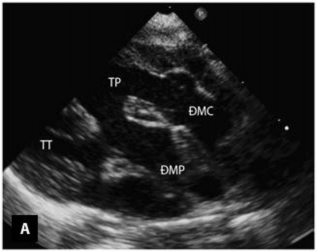

Mặt cắt cạnh ức trục dài cho phép đánh giá tình trạng liên tục giữa van hai lá - van ĐMC, tương quan và vị trí của hai đại động mạch (Hình 1.14) [84].

Hình 1.14: Hình ảnh TPHĐR thể TLT sử dụng mặt cắt cạnh ức trục dài [34]